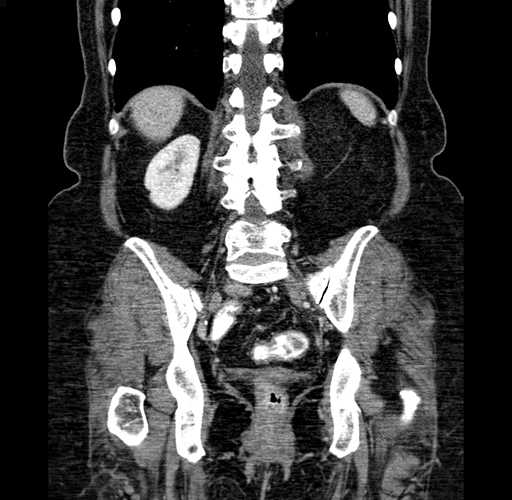

Pre-Chemo: Axial Venous

Pre-Chemo: Coronal Venous